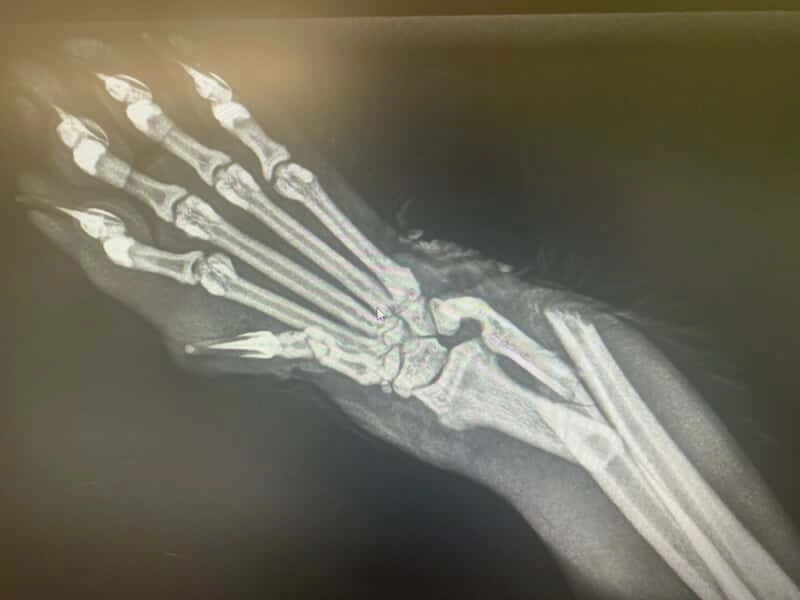

Po pilnej konsultacji w lecznicy w Zgorzelcu okazało się, że Fruszek ma złamane obie kości przedramienia. Ratunkiem jest operacja ze stabilizacją płytą i śrubami - zabieg zaplanowano na jutro. To jedyna szansa, by uratować łapkę i dać mu życie bez bólu. Prawdopodobnie został potrącony przez auto.